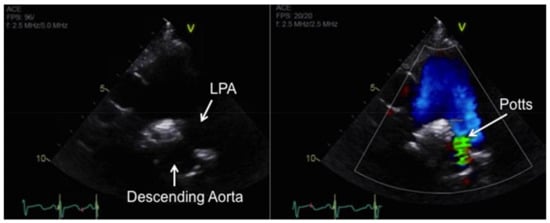

Although pediatric-specific evidence is lacking, medical management of children based on clinical experience follows a similar algorithm to that of adults treated with IPAH [3,7,8]. For patients whose disease progresses despite maximal medical therapy, the surgical options include lung transplantation or a Potts shunt—creation of a left pulmonary artery to descending aorta connection in an effort to facilitate right-to-left shunting [9]. This procedure can provide effective palliation in carefully selected children with end-stage pulmonary vascular disease and suprasystemic PAH [10].

The general indications for atrial septostomy include severe pulmonary hypertension, syncope, intractable heart failure refractory to chronic PAH-targeted therapy, and symptomatic low cardiac output state [179,180]. Risks associated with this procedure include worsening of hypoxemia with resultant right ventricular ischemia, worsening right ventricular failure, increased left atrial pressure, and pulmonary edema. We favor a graded balloon dilation approach utilizing intra-procedure echo guidance and saturation monitoring to determine the adequacy of shunting. A Potts shunt—connection of the left pulmonary artery to descending aorta (Figure 16)—can be considered in cases of severe, refractory PAH with suprasystemic PA pressures and adequate RV function to allow an immediate reduction in right ventricular afterload [10,181,182,183]. The choice of initial atrial septostomy versus Potts shunt for patients failing medical therapy is a source of ongoing debate.

Figure 16.

Echocardiogram of the Potts shunt in a patient with severe IPAH by 2D imaging (left) and with color Doppler (right). LPA, left pulmonary artery.